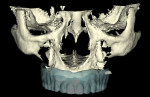

Ten radiopaque markers (gutta percha, Hygenic®, Coltène/Whaledent Group, www.coltene.com) were placed in the maxillary complete denture to prepare the denture for a specific guided- surgery protocol (NobelClinician™ Software, Nobel Biocare USA, LLC, www.nobelbiocare.com).23-30 This protocol uses a dual cone beam computed tomography (CBCT) scan procedure. The first CBCT scan (i-CAT®, Imaging Sciences International Inc., www.imagingsciences.com) was taken with the patient’s dentures in place, and a second CBCT scan was taken of the maxillary complete denture alone. The two scans were exported in Digital Imaging and Communications in Medicine (DICOM) format and loaded into the guided-surgery software, where a 3-dimensional (3-D) virtual working model of the patient was generated (Figure 4 through Figure 7) to enable virtual implant planning to be performed. Because the patient’s denture contained the approved esthetic arrangement of the teeth, the implants could be placed virtually in the most prosthetically favorable position.